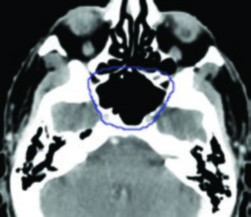

Na prática clínica, a escolha do algoritmo deve considerar o sítio anatômico e o cenário clínico. Para planejamentos em abdome, pelve ou cabeça e pescoço — onde as heterogeneidades são menos dramáticas — mesmo um pencil beam pode ser aceitável para planejamento forward, embora um algoritmo tipo “b” seja sempre preferível. Para pulmão, mama com campo tangencial passando por pulmão, mediastino, ou qualquer situação com campos pequenos de alta energia, um algoritmo tipo “b” (CCC, AAA, Monte Carlo ou Acuros) é essencial e não-negociável.